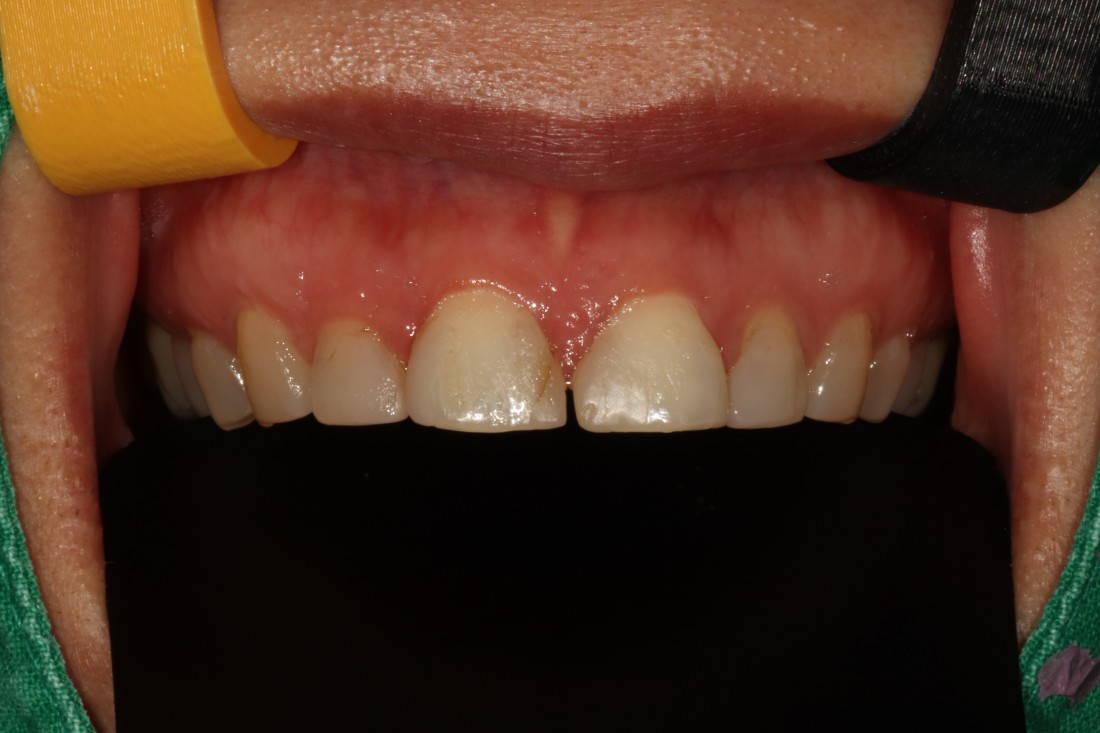

그렇지만 실제로 라미네이트 전/후 사례를

200케이스 가까이 공유하는

라미네이트 치과를 찾기는

쉽지 않은데요.

광주 무삭제 라미네이트 치과는

벌어진 앞니 / 깨진 앞니 /

얼룩덜룩한 앞니 / 왜소치 등

다양한 사례의 라미네이트 전-후 사진을

투명하게 공개하고 있습니다.